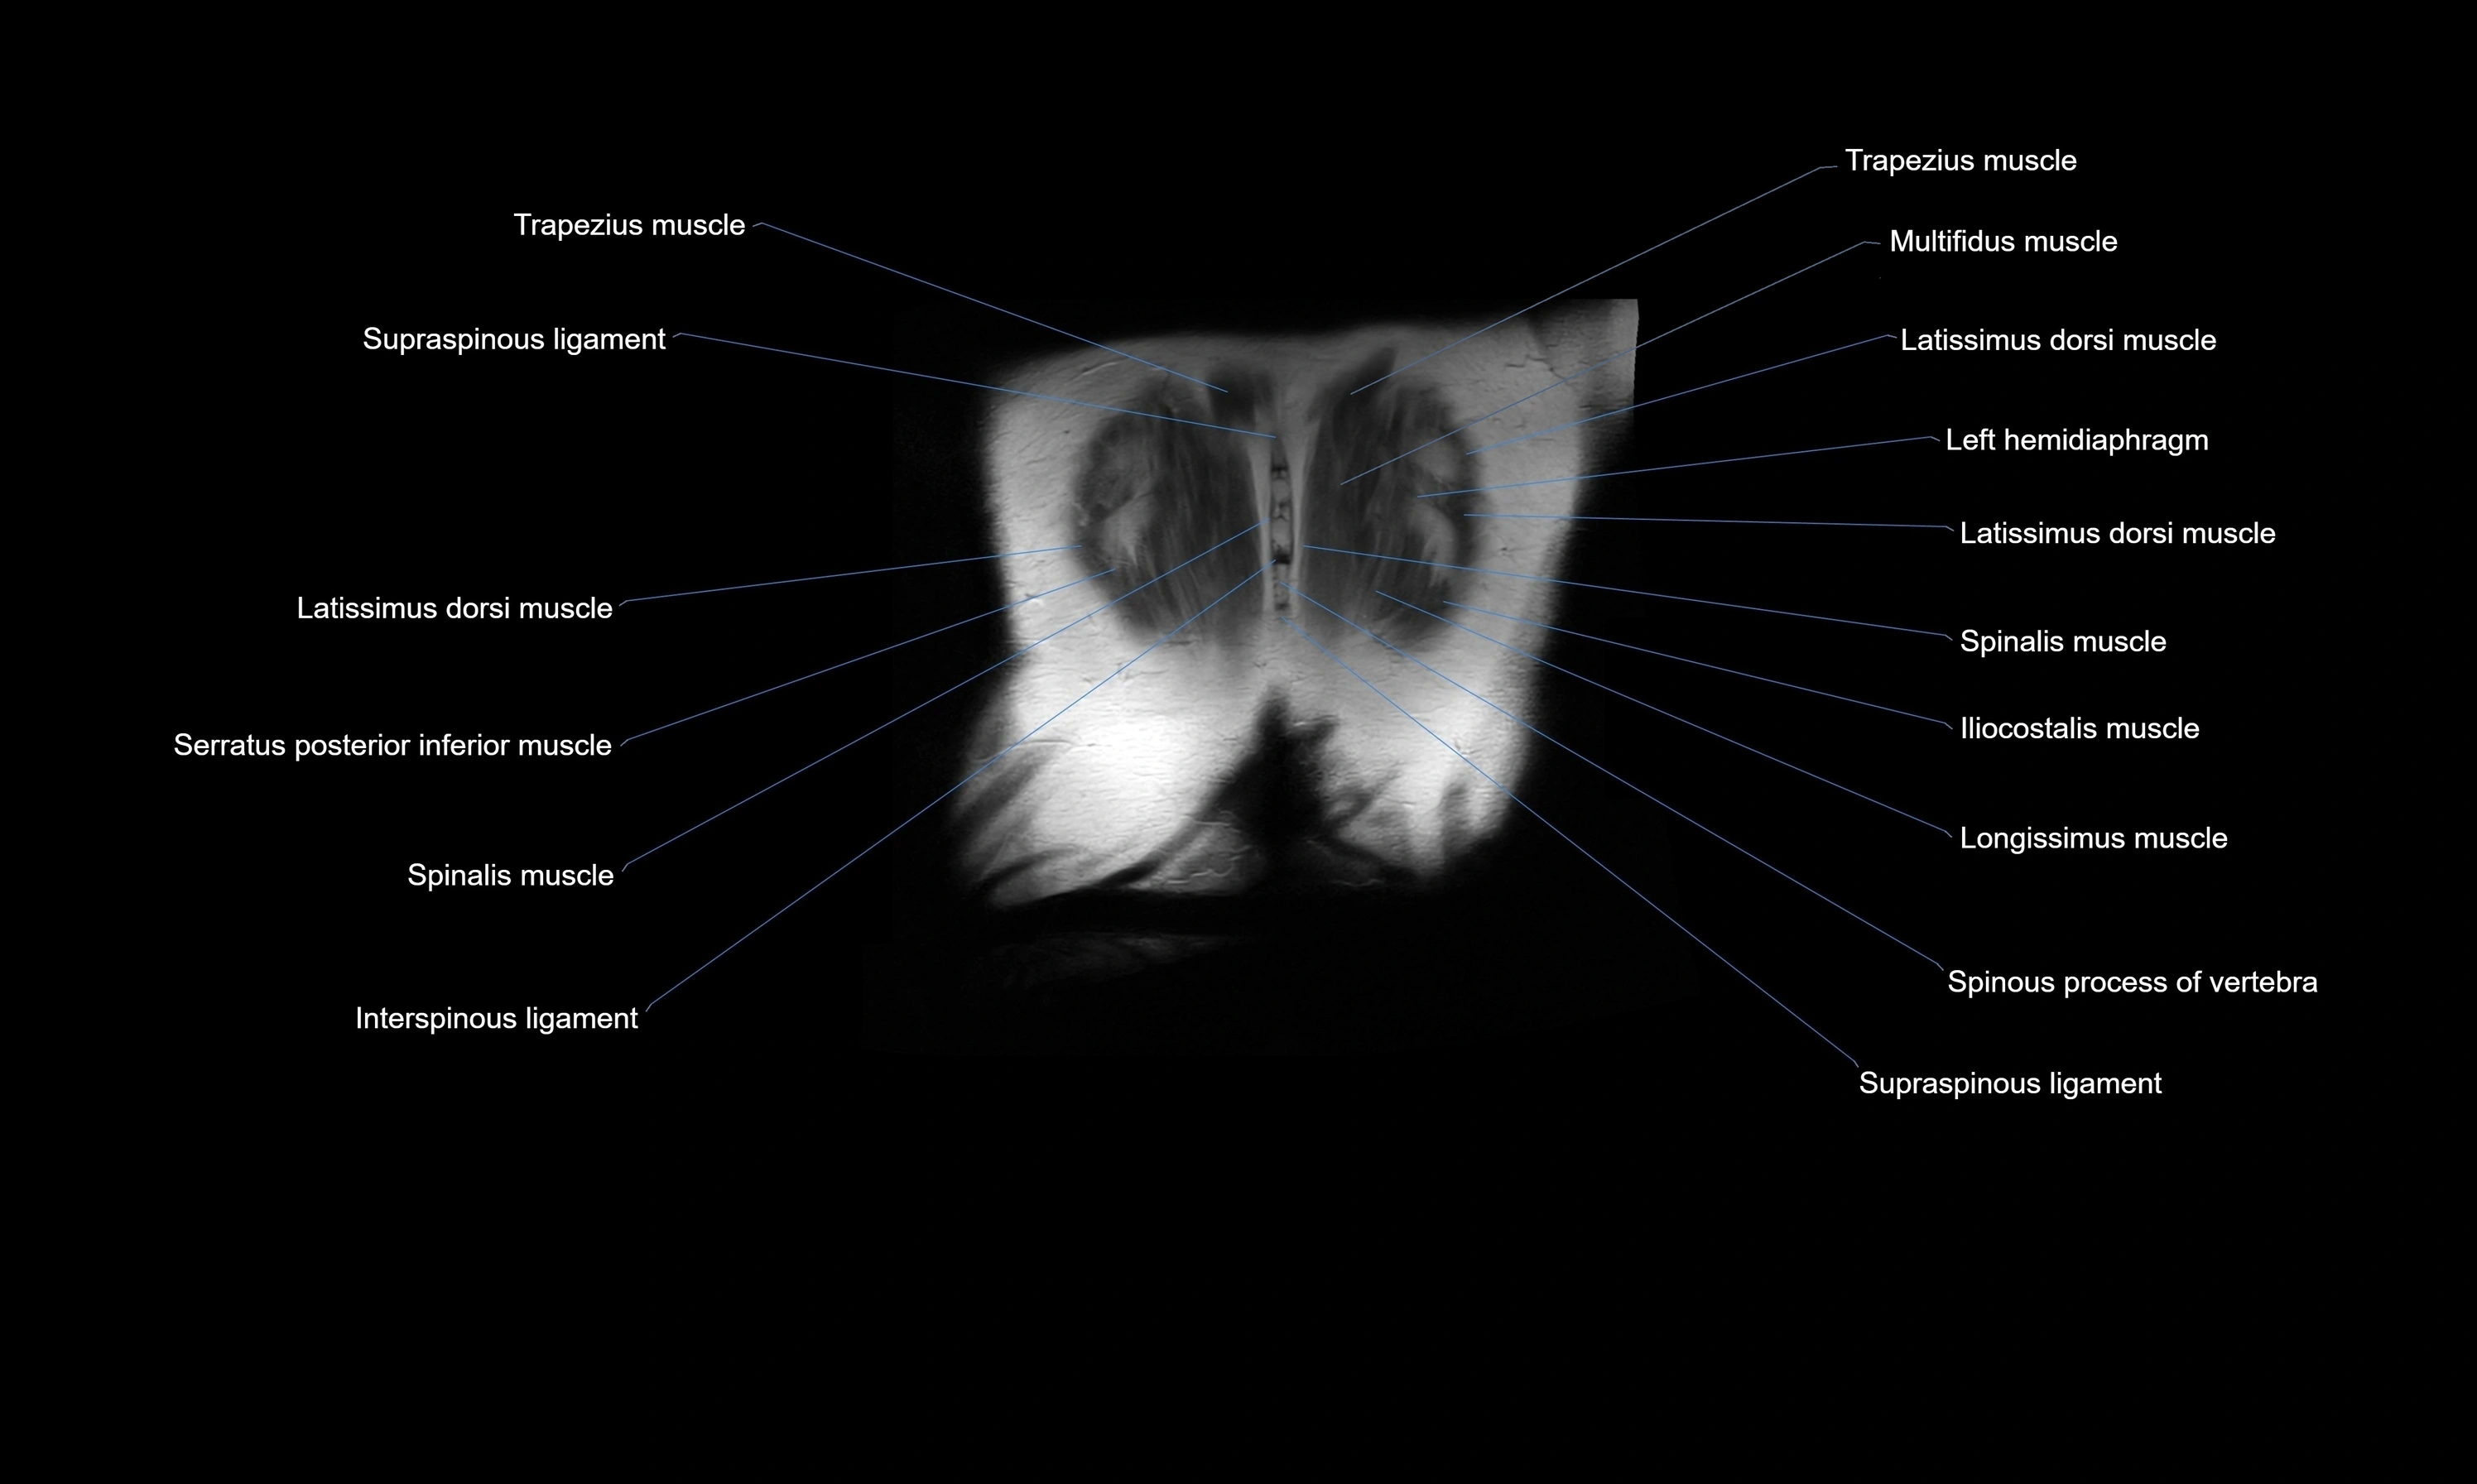

- Erector spinae muscles

- Interspinous ligament

- Latissimus dorsi muscle

- Left hemidiaphragm

- Serratus posterior inferior muscle

- Spinalis thoracis muscle

- Supraspinous ligament